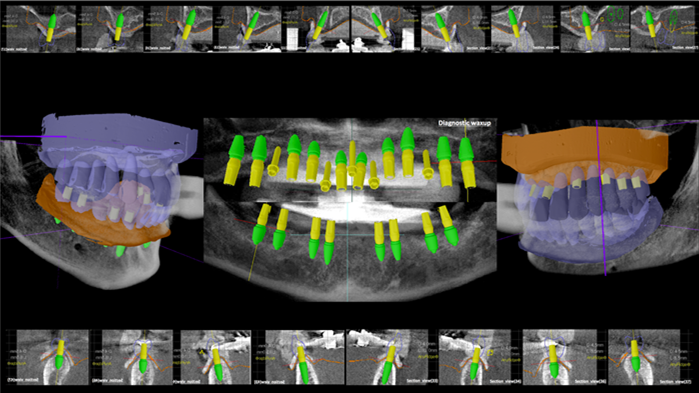

Clinical case: Preview the final goal first, make the ideal treatment plan, then realize it using the appropriate tools

- Courtesy of Dr. Sang Tack Lee, Korea -

Dr. Sang Tack Lee, edentulous, digital full mouth prosthetics, digital guided surgery, #11, #13, #14, #16, #17, #21, #23, #24, #26, #27, #33, #34, #36, #37, #43, #44, #46, #47, guided surgery, flapless, AnyRidge, R2GATE, Mega ISQ, MEG Torq, MEG Engine, R2GATE Full surgical kit